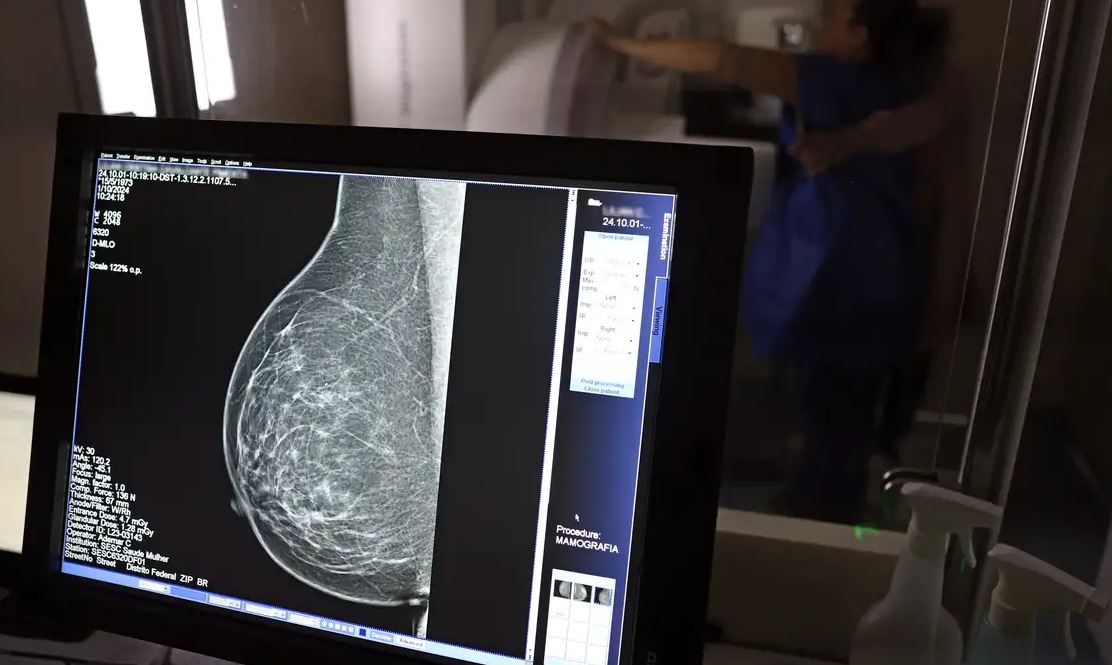

Uma lei publicada, nessa segunda-feira, 06, reforça o direito de trabalhadores com carteira assinada de se ausentarem por até três dias ao ano para a realização de exames preventivos de câncer, sem desconto no salário. A norma, que já constava na Consolidação das Leis do Trabalho (CLT) desde 2018, passa a obrigar as empresas a divulgarem o benefício, além de informações sobre campanhas de vacinação contra o HPV e o acesso a serviços de diagnóstico de câncer de mama, próstata e colo do útero.

- Câncer de mama;